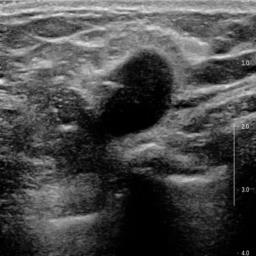

Ultrasonography is an important routine examination for breast cancer diagnosis, due to its non-invasive, radiation-free and low-cost properties. However, it is still not the first-line screening test for breast cancer due to its inherent limitations. It would be a tremendous success if we can precisely diagnose breast cancer by breast ultrasound images (BUS). Many learning-based computer-aided diagnostic methods have been proposed to achieve breast cancer diagnosis/lesion classification. However, most of them require a pre-define ROI and then classify the lesion inside the ROI. Conventional classification backbones, such as VGG16 and ResNet50, can achieve promising classification results with no ROI requirement. But these models lack interpretability, thus restricting their use in clinical practice. In this study, we propose a novel ROI-free model for breast cancer diagnosis in ultrasound images with interpretable feature representations. We leverage the anatomical prior knowledge that malignant and benign tumors have different spatial relationships between different tissue layers, and propose a HoVer-Transformer to formulate this prior knowledge. The proposed HoVer-Trans block extracts the inter- and intra-layer spatial information horizontally and vertically. We conduct and release an open dataset GDPH&GYFYY for breast cancer diagnosis in BUS. The proposed model is evaluated in three datasets by comparing with four CNN-based models and two vision transformer models via a five-fold cross validation. It achieves state-of-the-art classification performance with the best model interpretability.

翻译:超声波分析是乳腺癌诊断的一个重要常规检查,原因是其非侵入性、无辐射和低成本的特性。然而,由于其内在局限性,它仍不是乳腺癌的第一线筛选测试。如果我们能够精确地通过乳房超声图像诊断乳腺癌(BUS),它将是一个巨大的成功。我们提出了许多基于学习的计算机辅助诊断方法,以实现乳腺癌诊断/感官分类。然而,其中多数方法需要事先确定性能模型,然后对ROI内部的跨值进行分类。常规分类支柱,如VGG16和ResNet50等,可以在没有ROI要求的情况下实现有希望的分类结果。但是这些模型缺乏可解释性,从而限制了其在临床实践中的使用。在本研究中,我们提出了一个新的无乳腺癌诊断模型,在超声波图像中进行解释性特征描述。我们利用了先前的解剖学学学知识,即恶性肿瘤和良性肿瘤模型在不同组织层之间有着不同的空间关系,并提议采用状态解析法来编制这一先前的知识。拟议中的HOVer-Trans-Trading-Tradef-trainal Ex-deal-dealal-deal-deal-deal-degraphal-deal-deal-deal-deal-deal-deal disal disal-dal-dal-dal-dal-dal-deal-deal-dal-deal-deal-deal-dal-dal-dal-dal-dal-dal-dal-dal-dal-dal-dal-dal-dal-dal-I-dal-Iversal-dal-Ial-d-d-I-d-d-I-I-I-I-I-I-I-I-I-I-I-I-I-I-I-I-I-I-I-I-I-I-I-I-I-Ial-I-Ial-Ial-I-I-I-I-I-I-I-I-I-I-I-I-I-I-I-I-I-I-I-I-I-I-I-I-I-I-I-I-I-I-I-I-